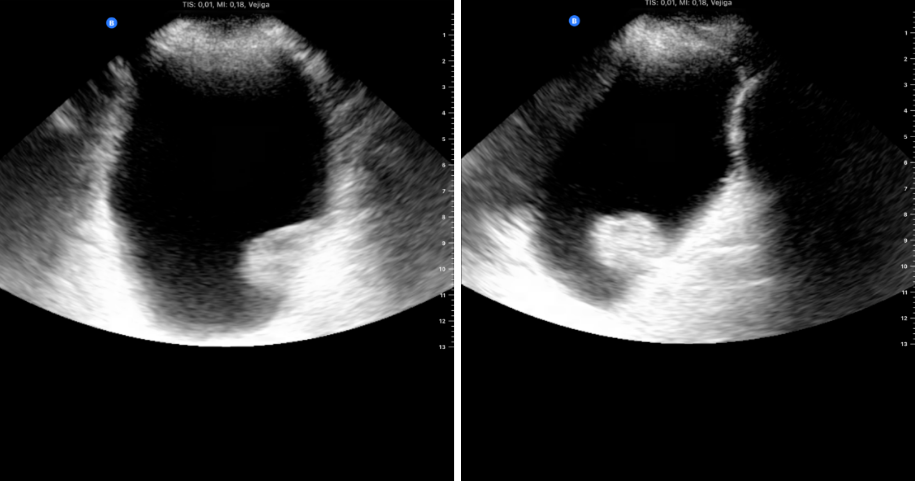

Ecoscopia clínica: izquierda, sonda cónvex en proyección transversal donde se objetiva la lesión en la pared lateral; derecha, proyección longitudinal donde se objetiva la misma lesión con una base pediculada.

Ecografía reglada: confirma lesión neoplásica con mismas características.

Uso complementario para descartar TVP (por sospecha de coágulo) y repetir ecografía vesical para valorar posible movilización del coágulo y control de resolución posterior.